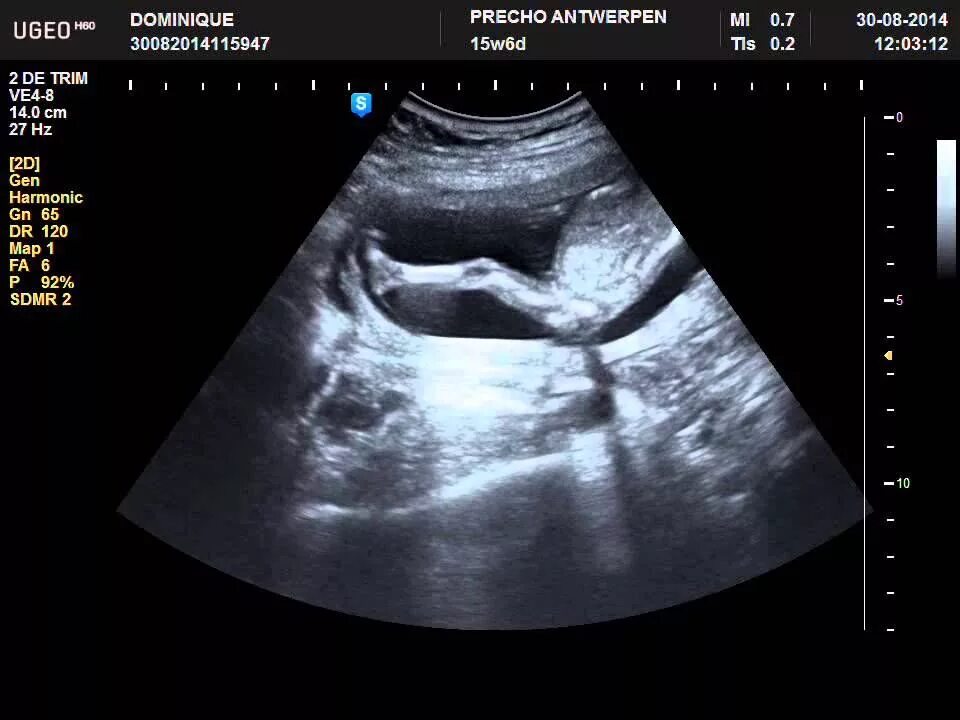

Беременность 15 недель развитие плода и ощущения